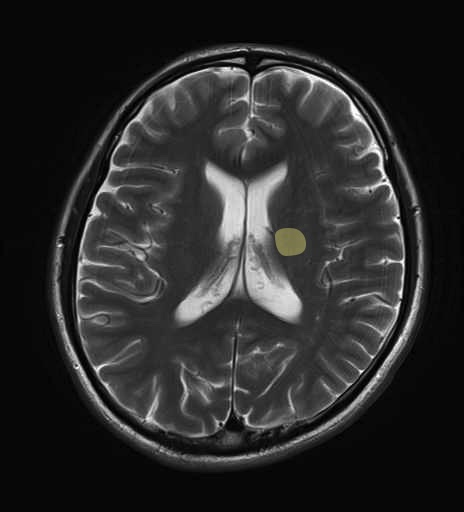

錐体路・皮質脊髄路のMRI画像解剖

運動系 錐体路系に色を付けました。

■皮質脊髄路(いわゆる錐体路):一次運動野から脊髄遠隔の下位運動ニューロン細胞体まで